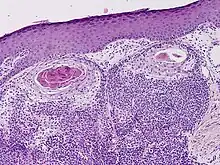

Clear cell hidradenocarcinoma

Hidradenocarcinoma (also known as malignant hidradenoma, malignant acrospiroma, clear cell eccrine carcinoma, or primary mucoepidermoid cutaneous carcinoma) is a malignant adnexal tumor of the sweat gland. It is the malignant variant of the benign hidradenoma. It may develop de novo or in association with an existent hidradenoma.[1]